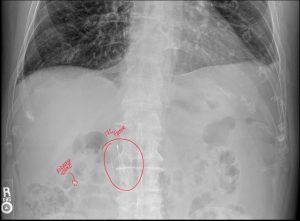

A 45-year-old male patient presented with acute lower back pain after a lifting injury. During the physical examination, the chiropractor noted tenderness and a significantly limited range of motion in the lumbar region.

Given the severity of the symptoms, the chiropractor decided to take X-rays. The images revealed a small, previously undiagnosed compression fracture in one of the lumbar vertebrae. This finding significantly altered the treatment plan, shifting from manual adjustments to a referral to an orthopedic surgeon.